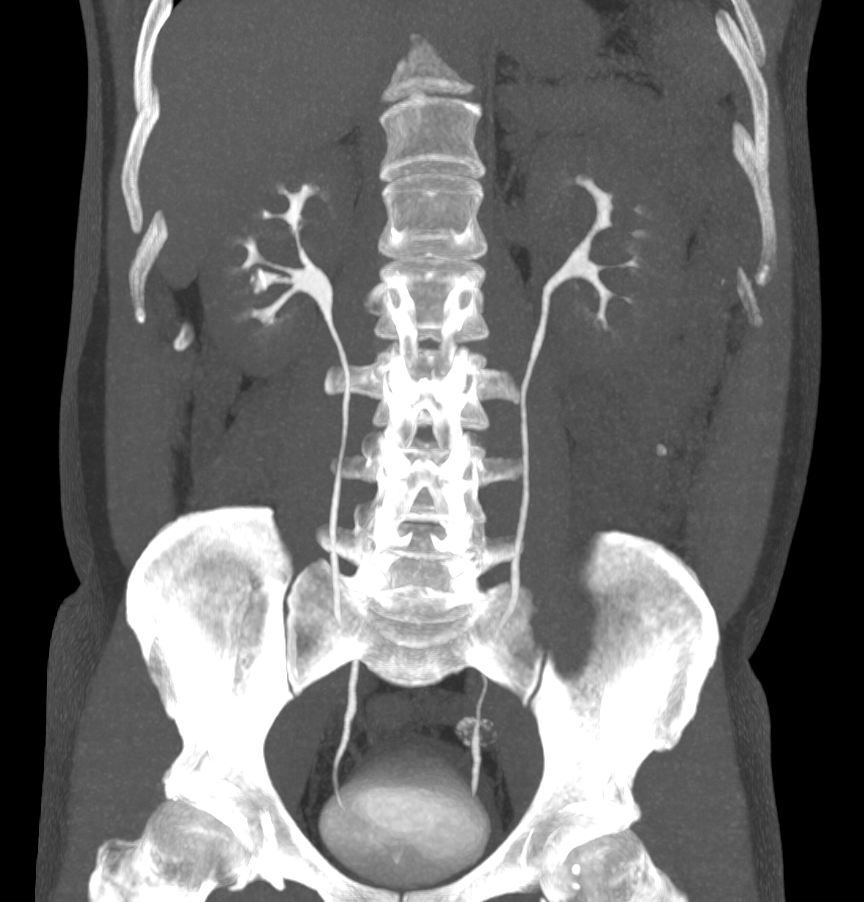

Данный формат позволяет проводить угловые и линейные измерения, изменять яркость, контрастность. Исходные данные, полученные при томографии, используются:

- для реформатирования изображений в различных плоскостях;

- трехмерных реконструкций.